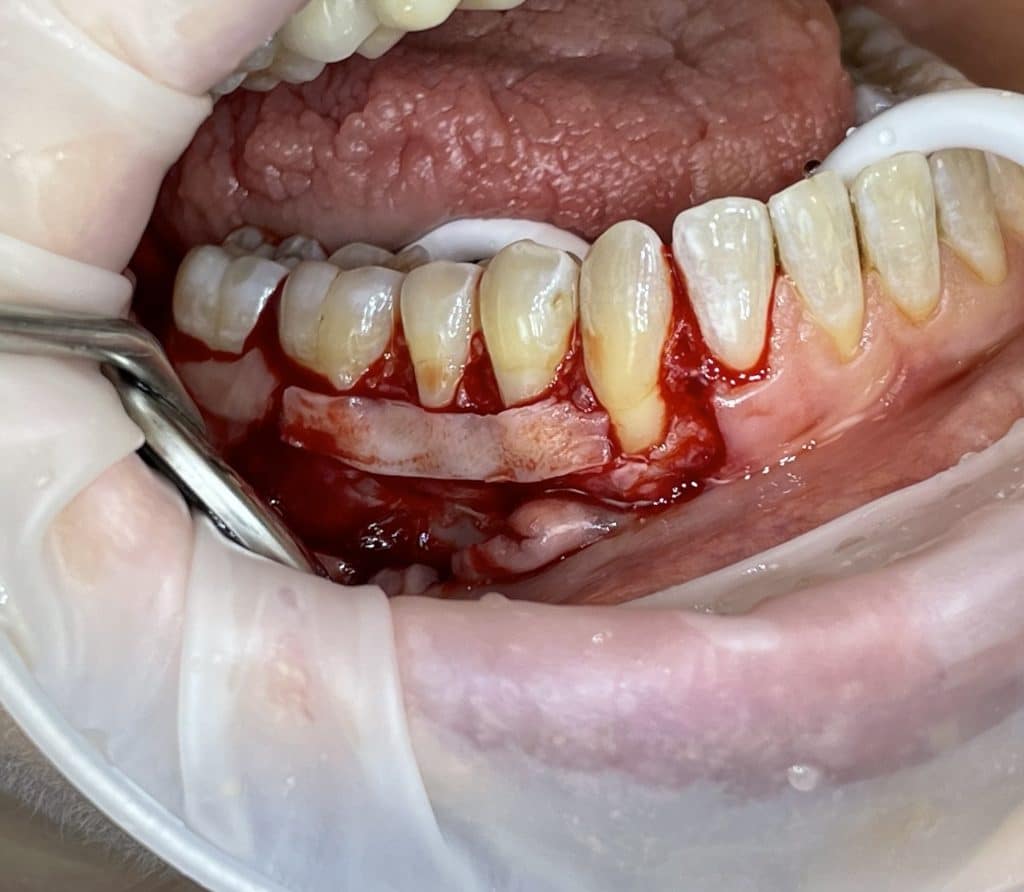

In quadrant 4, we initially proceeded with the reconstruction of the cervical part of the teeth and, where present, the removal of caries. Subsequently, we performed a bilaminar technique for multiple gingival recessions using a trapezoidal-shaped flap and minimal relieving incisions. We harvested a connective tissue graft from the palate, which was sutured to the periosteum and then covered with the coronally advanced flap, following the bilaminar technique. The sutures were removed after 10 days.

connective tissue graft